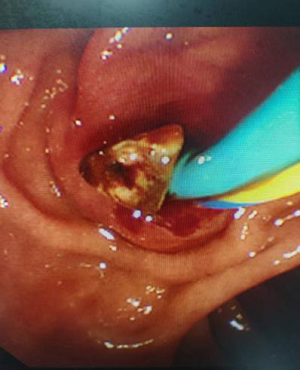

图片15

取出结石

9月19日,肝胆胰-甲状腺-血管外科医生为患者行“ERCP(经内镜逆行胰胆管造影)+EST(内镜下乳头括约肌切开术)+EPBD(内镜下乳头球囊扩张术)+胆管取石术+ENBD(内镜下鼻胆管引流术)+ERPD(内镜下胰管引流术)”手术。在内镜治疗下为患者取出胆总管结石,术后留置鼻胆管引流,两天后,患者拔除鼻胆管,一周后患者康复出院。

该患者成功应用ERCP技术取出胆总管内结石,同时保留了胆囊,缩短了住院时间,避免患者术后长期留置T管,给患者带来了极大的便利。